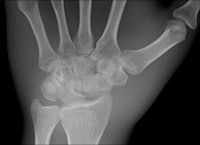

The multifunctional panels can be used in a number of clinical settings, including intensive care for bedside examinations, while portable DR detectors have created new applications in trauma, pediatric, and orthopedic settings.

The industry's first detector featuring wireless image transmission, the DRX-1 from Carestream, was introduced in 2009 at the University Hospital in Frankfurt and subjected to a series of studies by Vogl's group against conventional computed radiography (CR) systems for both image quality and workflow efficiency. As a result of the positive findings from the studies for superior image quality and dose efficiency, the DRX-1 detector is now used as part of routine protocol.

Identical in size to a standard CR cassette, the detector can be inserted into an existing wall stand or table Bucky and used in combination with existing x-ray generators from a number of original equipment manufacturers, presenting an attractive option for modest-budget facilities. The flexibility of the portable detector provides great advantages in time-critical environments where an x-ray image can now be captured and viewed in less than six seconds, he explained.